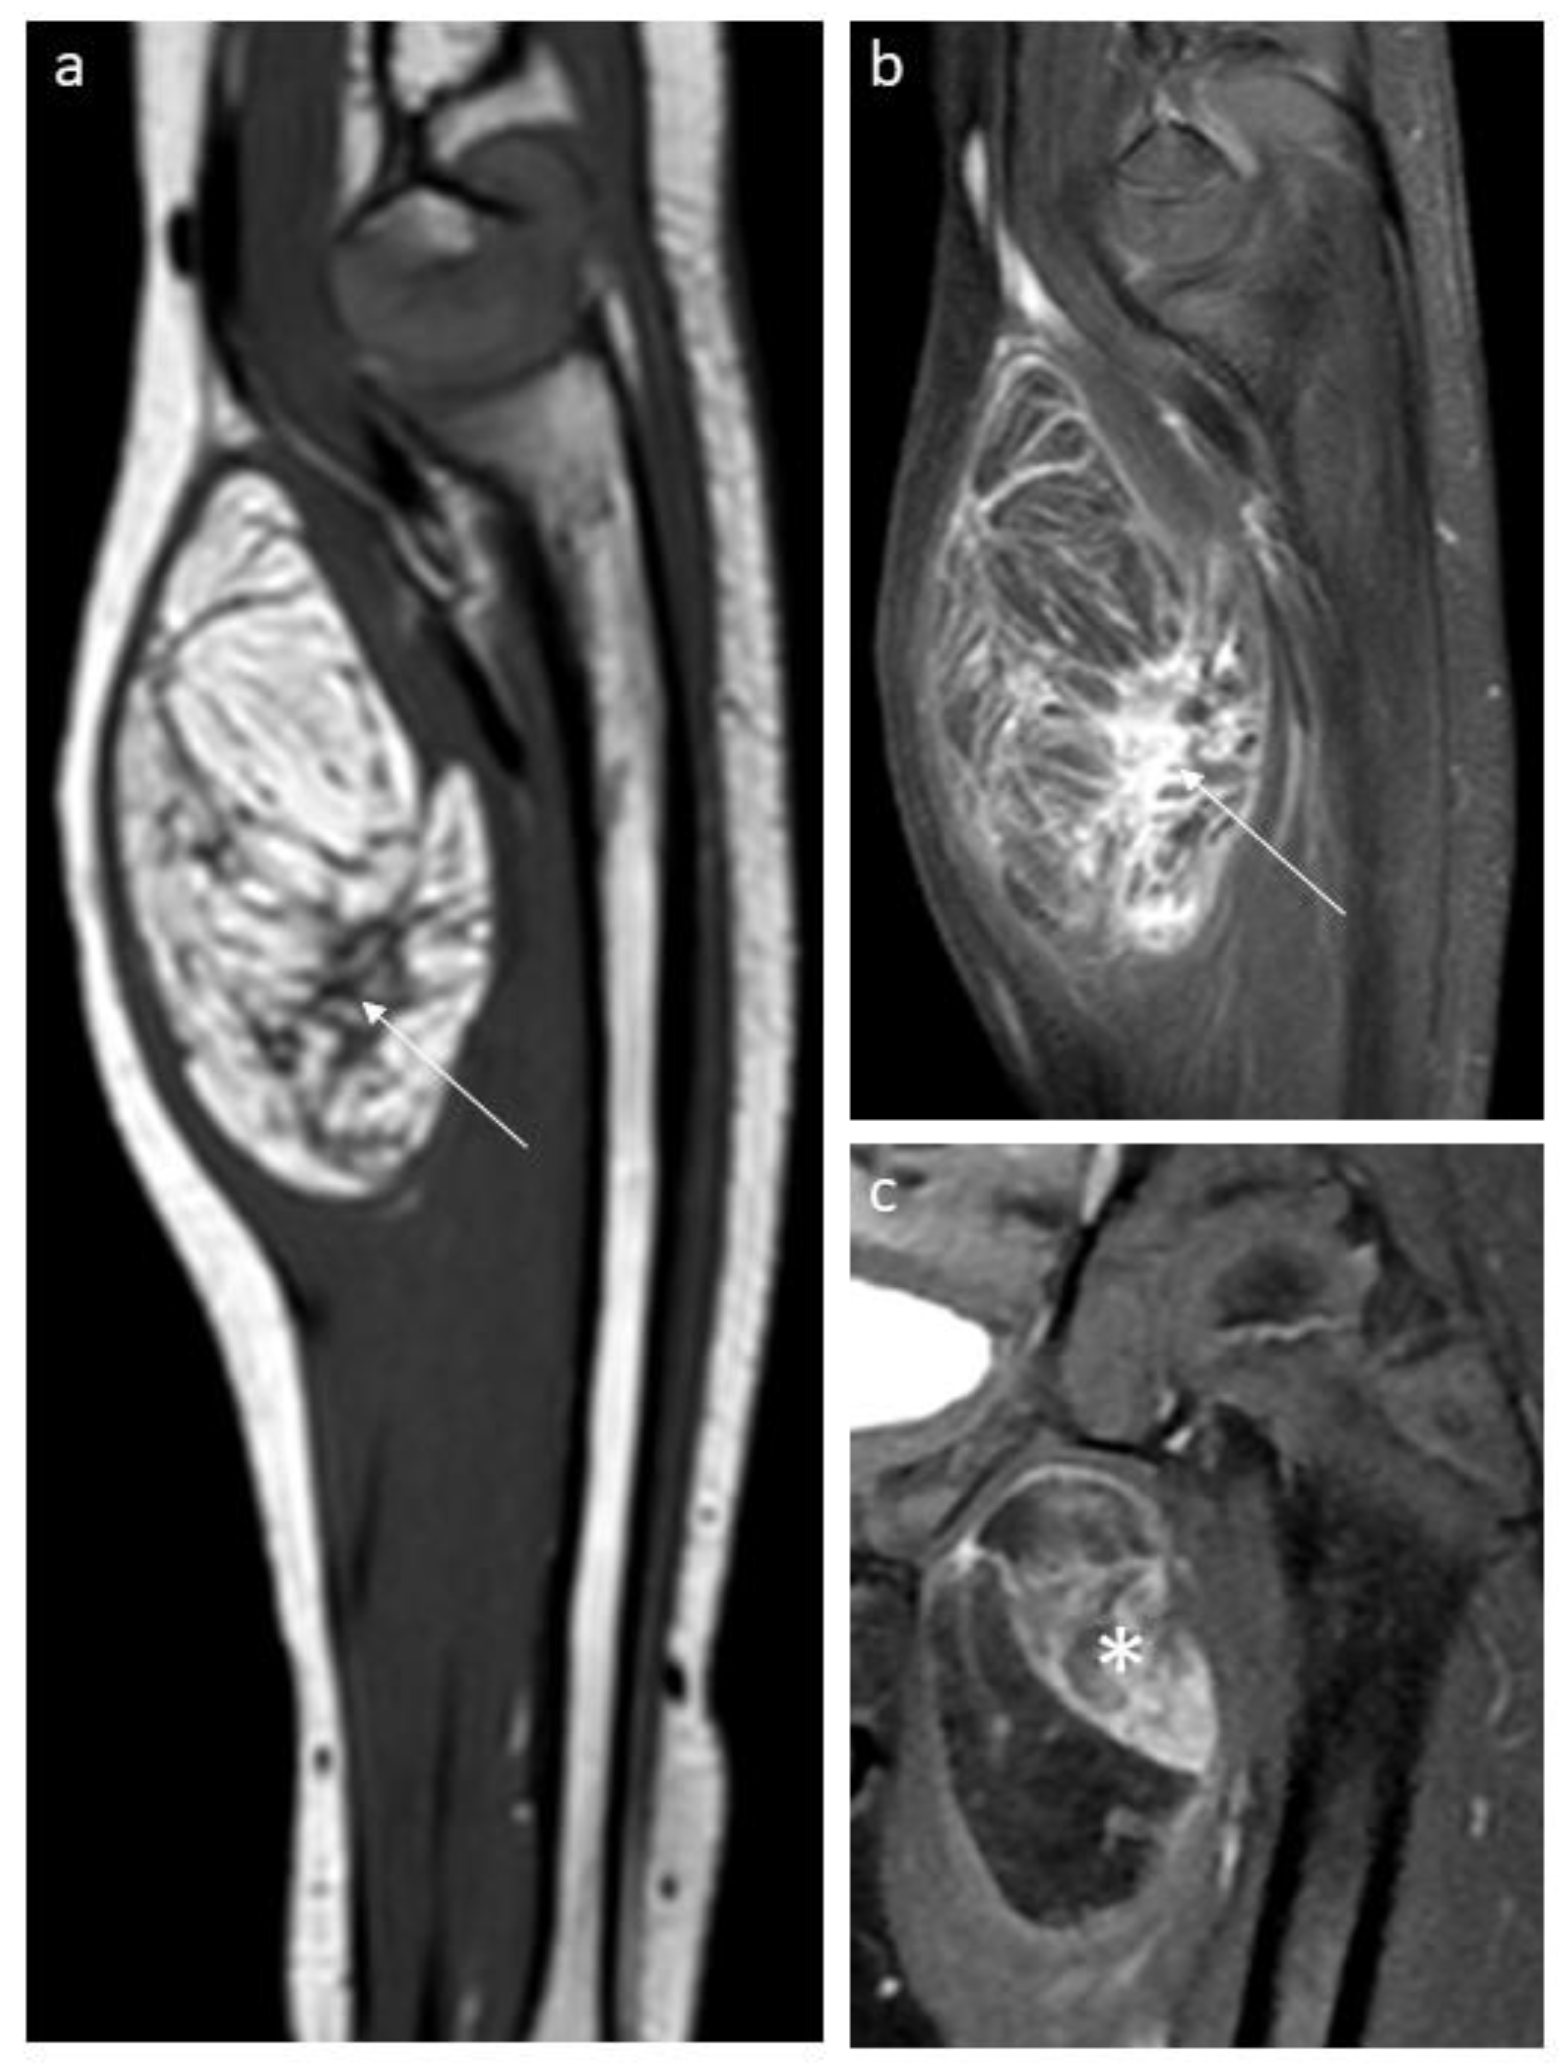

3.1. Lipoblastoma and Lipoma

3.3. Lipofibromatosis